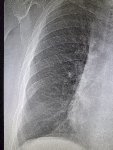

Здравствуй двачик, пишет вам простой рентгенолог из мухосранской поликлиники, сегодня я буду флексить зарплатой за ноябрь! Аж ПЯТЬДЕСЯТ ТРИ ТЫЩИ ПЕРЕВЕДУТ! С пруфом! А чего достигли вы? Ну и в доктора тож поиграем! Я буду вам картинки показывать, а вы пиздецомы находить! Найдите пиздецому на фтчк! Отчет еще по фог считать квартальный и годовой сегодня :-(